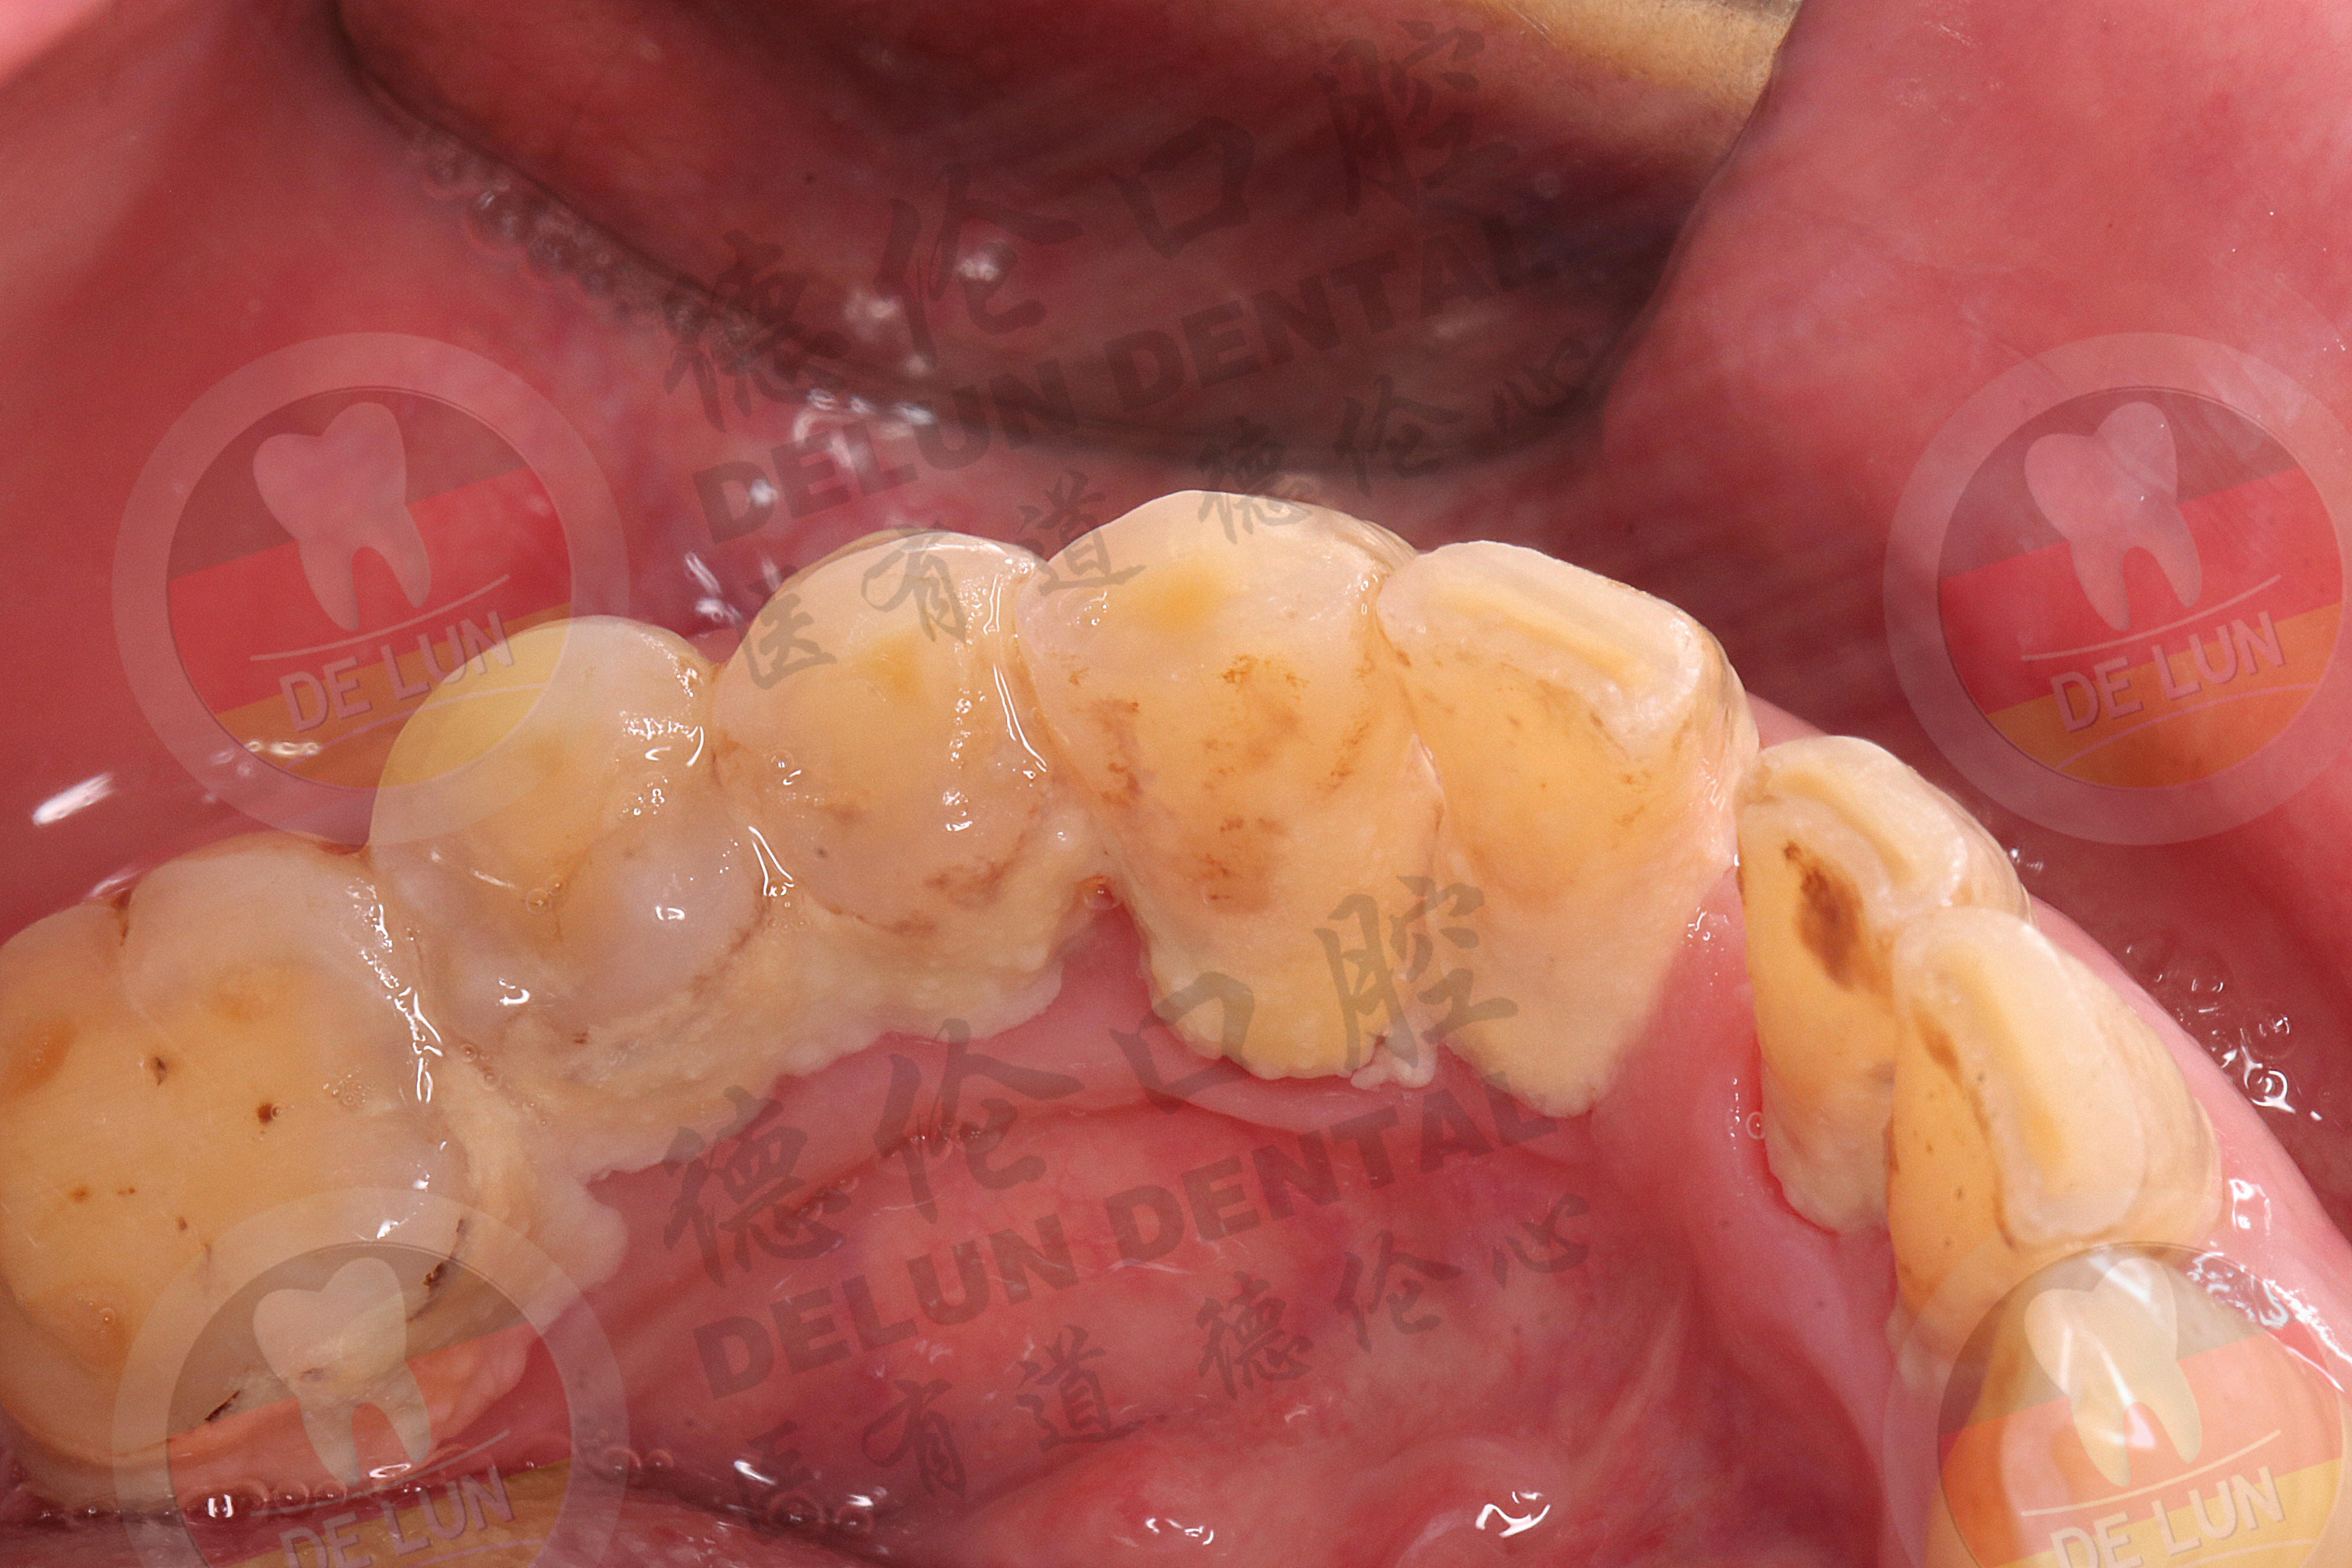

1.牙结石----可恢复

长期的牙结石不及时清理,会导致越来越多,久而久之就会导致牙龈萎缩。一般情况下,选择洗牙的方式清除掉牙结石,就可以把导致牙龈萎缩的刺激物去除,牙龈萎缩也就慢慢恢复。